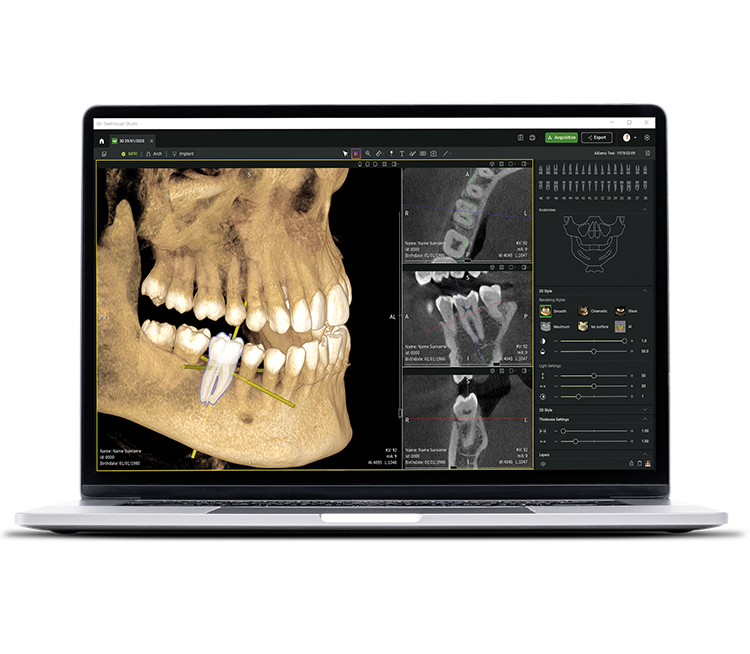

See tomorrow. See a new level.

Neben ausgereiften Hardware-Technologien ist die revolutionäre Seethrough Studio Software der entscheidende Faktor für den hohen Standard des gesamten W&H-Imaging Portfolios: Mit nützlichen Funktionen und fortschrittlichen Algorithmen ist Seethrough Studio eine Komplettlösung, die die Bildgebung und digitale Workflows in der Zahnmedizin auf ein neues Niveau hebt.

Scharfe, detaillierte und unverzerrte Bilder

dank der fortschrittlichen Algorithmen von Seethrough Studio.

Integriertes Implantatplanungstool

Über die herausragende Bildqualitätund die intuitive Bedienung hinaus bietet Seethrough Studio zahlreiche nützliche Funktionen wie etwa das standardmäßig integrierte Implantatplanungstool für eine einfache Visualisierung und Vorbereitung der Behandlung.

KI-unterstützte Funktionen

Seethrough Studio verwendet Verfahren der künstlichen Intelligenz zur Unterstützung der Visualisierung und Verwaltung klinischer Bilddaten. Die Software stellt automatisierte Funktionen bereit, einschließlich der Segmentierung relevanter anatomischer Strukturen in 3D-Volumenmodellen, der Ausrichtung einzelner Zahnachsen, der Generierung der Zahnbogenkurve sowie der Nachverfolgung (Tracing) des Nervus alveolaris inferior.